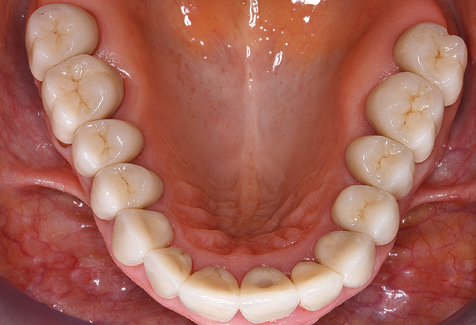

Un'assistenza standardizzata e regolare a misura di rischio nell'ambito di SPT è la chiave per il successo del trattamento clinico a lungo termine nei pazienti con situazione periodontale compromessa. Ciò è particolarmente vero per i pazienti a cui vengono applicati impianti dopo il trattamento parodontale completato con successo (Fig. 11a e b).